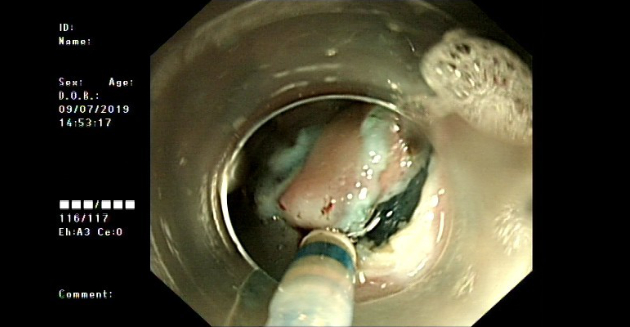

2019?, ??? ??? ???? ??? gastric antrum?? lesser curvature? submucosal bulging mass? ?????? submucosal ectopic pancreas? ???????. (?? 2)

??? ?? ??? ??? ?? contraindication ?? ??? ????, ???? endoscopic submucosal dissection(ESD)? ??.

Mucosa?? ??? ectopic pancreatic tissue? ??? gastric mucosa? ??? ???? ??? ??..